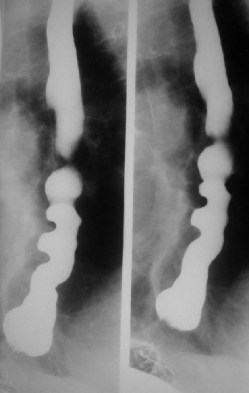

SIGNO DEL PICO

Signo de vólvulo y otras causas de obstrucción intestinal en asa cerrada, que inicialmente se describió en el estudio baritado (enema opaco). Se refiere a la estenosis fusiforme que se dirige al punto de torsión (flecha roja en la radiografía y flecha negra en el esquema). En caso de que el contraste atraviese la estenosis y exista una disminución de la luz en el segmento proximal de la torsión, la imagen obtenida recuerda a la de dos pájaros con sus picos juntos.

La imagen muestran el Signo del pico en un paciente con un vólvulo de sigma.

Aunque lo hemos incluido dentro de los signos de colon, este signo también es visible en las obstrucciones en asa cerrada de intestino delgado.

Inicialmente descrito en el enema opaco, en la TC también es visible este signo y no solamente en el asa eferente (como ocurre en el enema opaco, donde este asa se rellena retrógradamente) sino también en el aferente.

Existe otro Signo del pico en la achalasia, afectando al esófago distal, ya descrito en la sección correspondiente (ABDOMEN/Tubo digestivo/Esófago).